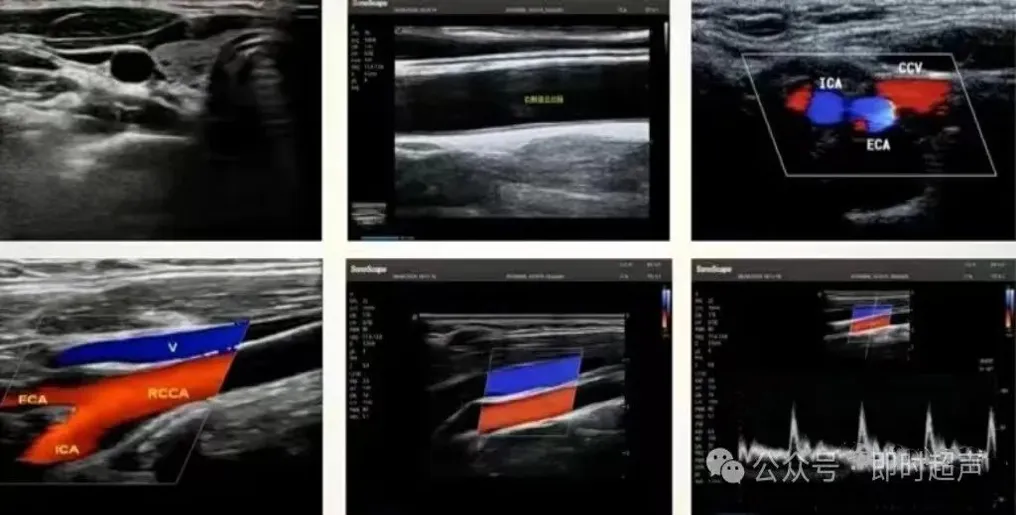

颈内、外动脉检测鉴别

正常声像图要点

● 颈动脉、椎动脉走行正常,内径正常,内-中膜光滑,厚度<1.0mm,内壁未见明显异常回声。CDFI、PW:颈动、主动脉管径内血流充盈良好,内未见明显异常回声,频谱形态正常,流速正常。

● 颈内静脉走行正常,内径正常,塌陷良好,管腔内未见明显异常回声,CDFI、PW;颈内静脉内血流充盈良好,频谱形态正常,流速正常。